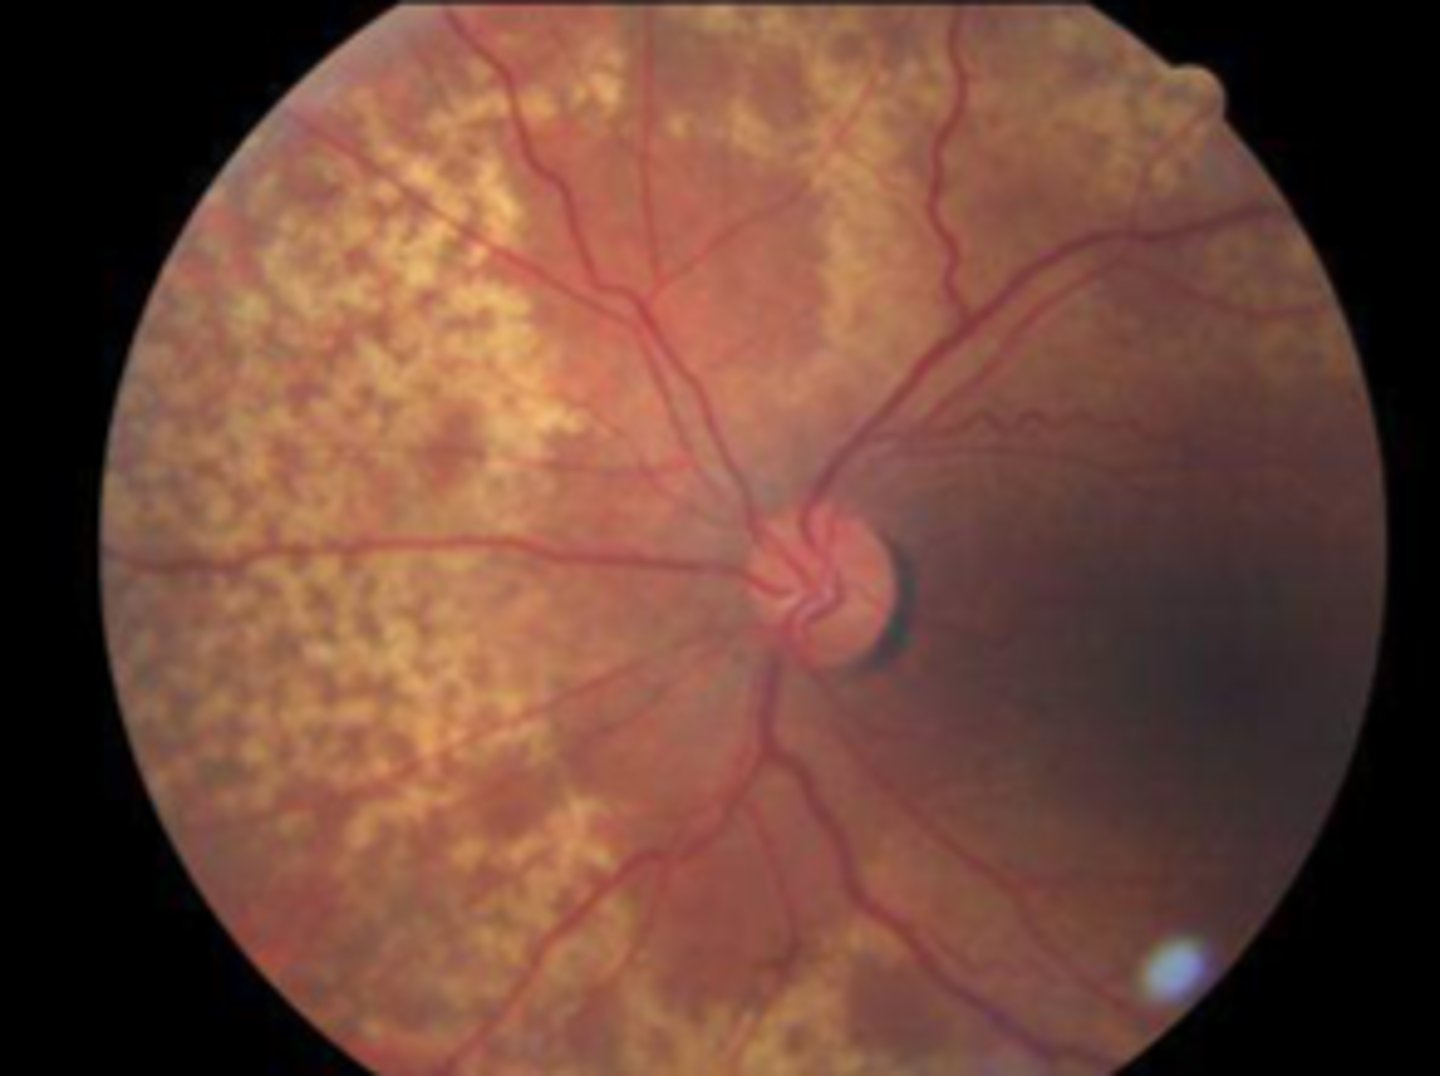

Peripheral pigmentary (reticular) degeneration: aetiology

• Polygonal, honeycomb pattern of granular pigmentation

• Retinal periphery

• Occurs in 20% over age 40 and increases with age

• Benign

Peripheral pigmentary (reticular) degeneration: differential diagnosis

Retinitis pigmentosa